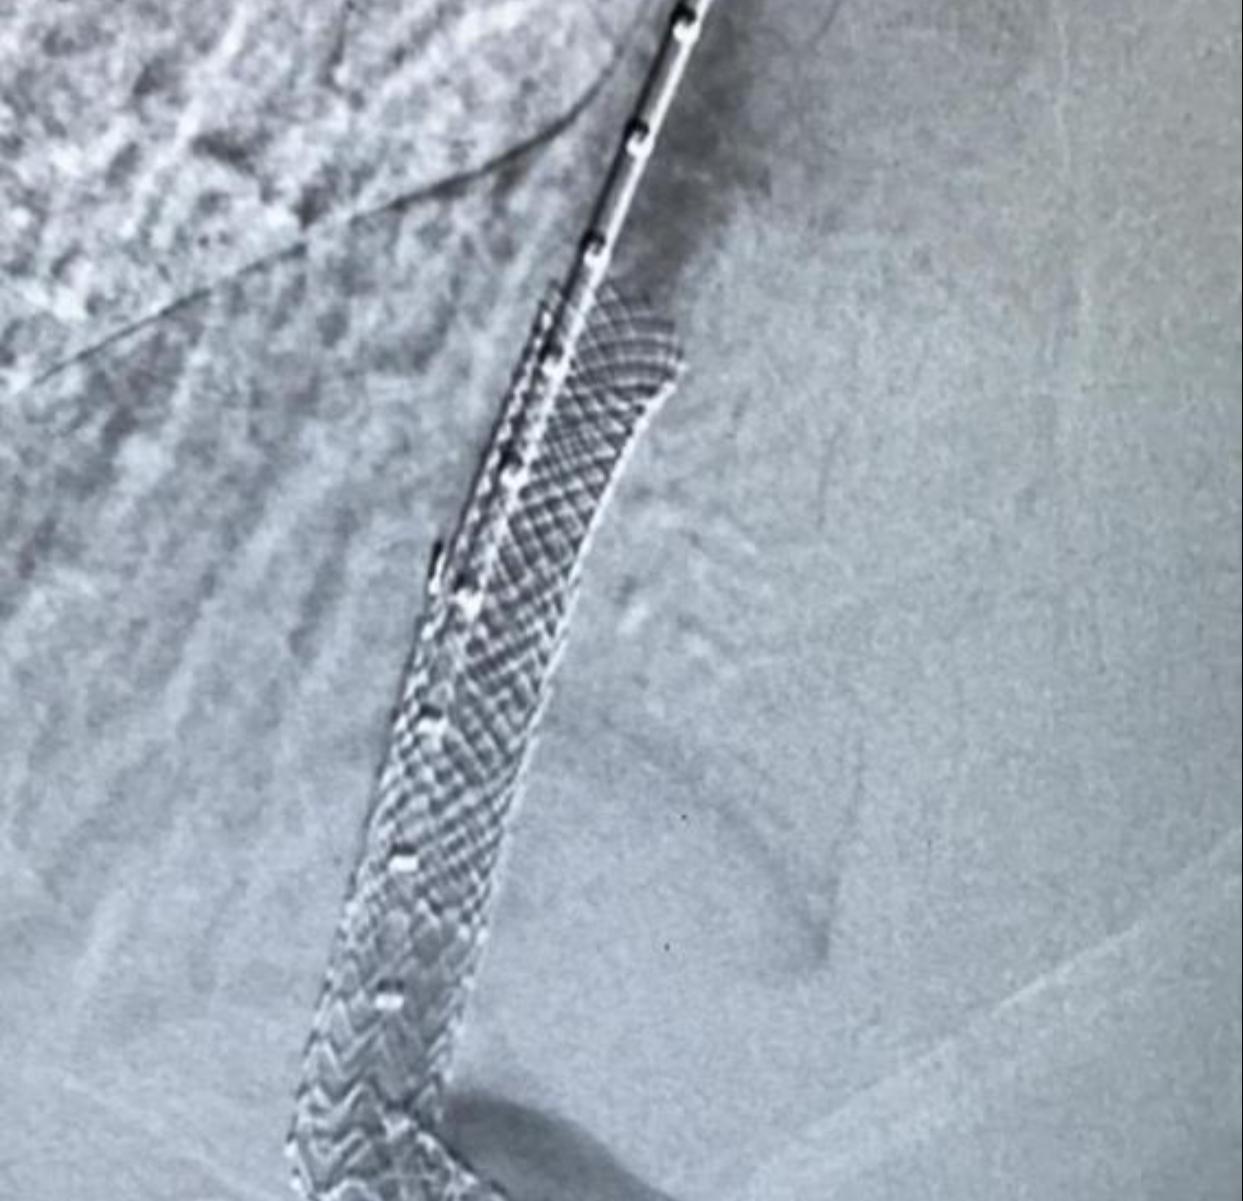

وعلى الفور تم تحويل المريض إلى قسم الأشعة التداخلية والقسطرة حيث تمكن الفريق الطبي المختص من إجراء القسطرة وتركيب دعامة بين الوريد البابي والوريد الكبدي وذلك في عملية استغرقت 5 ساعات.

- تركيب دعامة بين الوريد البابي والوريد الكبدي